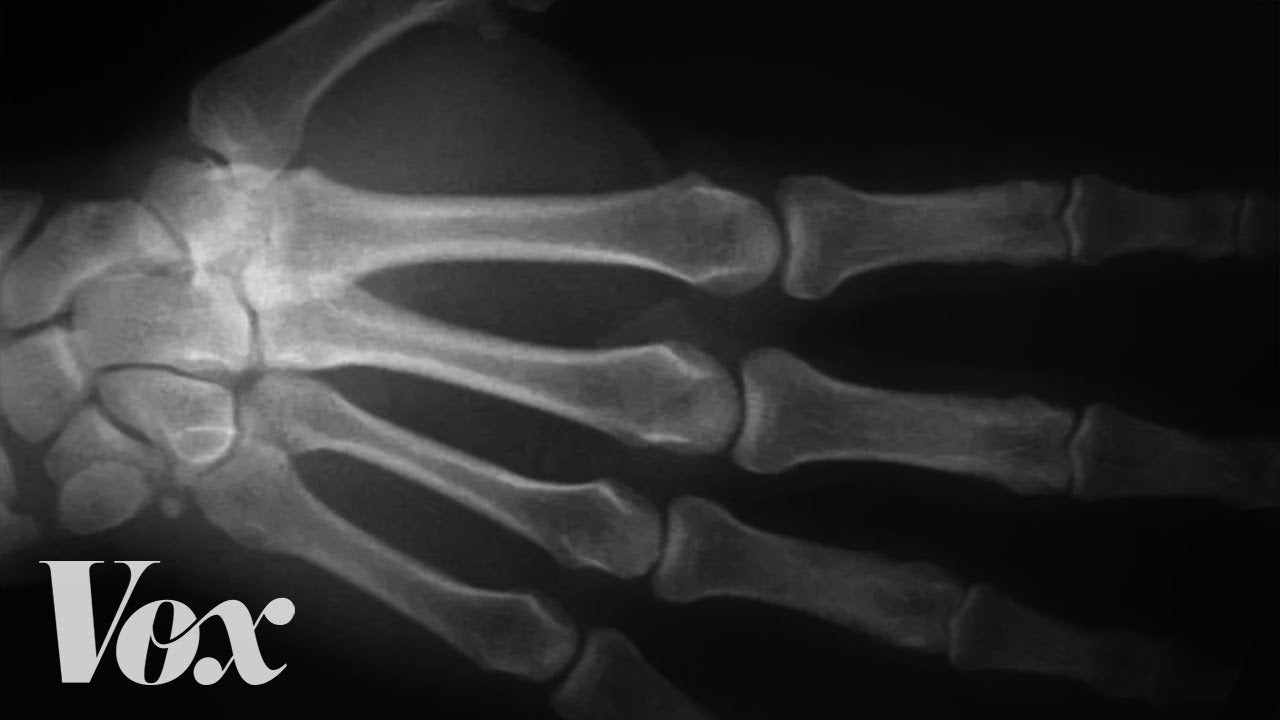

Es uno de esos pequeños grandes misterios del día a día. Si cierras la mano y aprietas los nudillos con la palma de la otra mano puedes llegar a escuchar un característico sonido como un “pop” que sale de cada articulación y que algunas personas encuentran muy satisfactorio. ¿Qué es lo que hace que los…